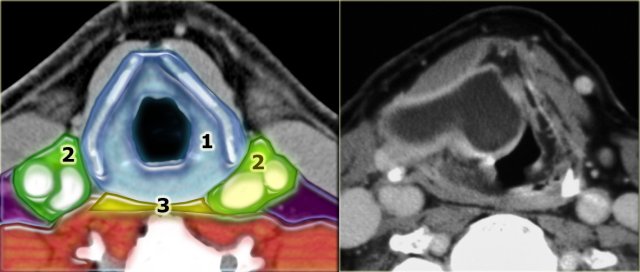

On the left a CT image of a patient with massive subcutaneous emphysema after a motor vehicle accident.

Air has dissected along the layers of the cervical fascia.

Notice that you are able to find all five spaces - they are now outlined by air.